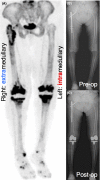

NaF PET assessment of bone metabolic changes around the femoral canal by intramedullary femoral alignment technique in total knee arthroplasty

We used the NaF PET scan to assess osteometabolic changes around the distal half of the femoral canal by intramedullary (IM) drill for femoral IM guiding rod insertion in total knee arthroplasty. Gentle IM rod insertion and focused attention can minimize surgical stress-induced biological reaction of the femoral IM canal.